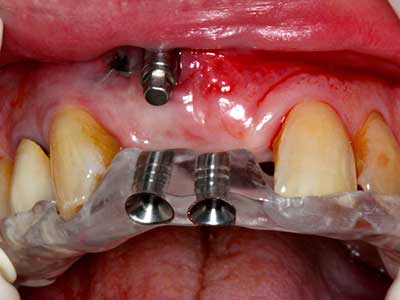

En la extracción de bloques óseos la piezocirugía también presenta ventajas adicionales: Además de la alta precisión en la osteotomía que ya se ha descrito antes, se ha comprobado que el uso de los delgados insertos de sierra resulta especialmente cuidadosas con el hueso. Frente a esto, sobre todo cuando se usan las fresas de Lindemann, cabe esperar pérdidas en la extracción significativamente más altas debido al mayor grosor de la parte frontal del cabezal (Lakshmiganthan, Gokulanathan et al. 2012). La separación basal que se necesita en particular en los injertos de bloque extraídos de forma retromolar se ve facilitada mediante sierras perpendiculares especialmente previstas a tal fin, lo que permite considerar que la cirugía piezoeléctrica es un procedimiento preciso y seguro para la obtención de bloques de hueso en el área retromolar (Happe 2007) (fig. 1-12).